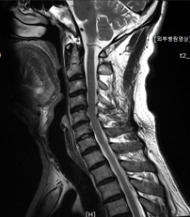

0613(1)_1.jpg 경추 엑스레이 사진

61세의 남성분은 경추부 방사선촬영에서, 측만증과 C5-6-7-T1의 디스크 공간이 좁아지고 C4-5 척추의 불안정성 소견이 보여서 경추부 MRI 검사를 시행하게 되었습니다.